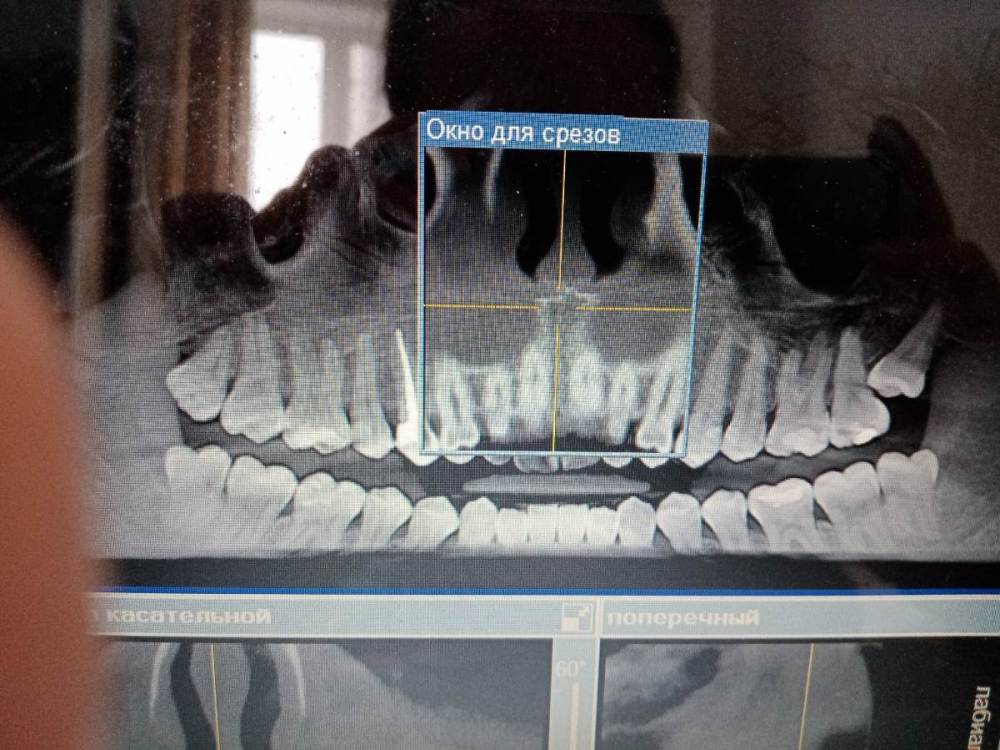

Анюсик Опубликовано 17 июля, 2021 Поделиться Опубликовано 17 июля, 2021 Добрый день! Ситуация такая, удалила ретенированнную дистопированную 8-ку.Она меня особо не беспокоила, просто за ней всегда скапливалась пища и прорезалась она с сильным насморком, я решила посмотреть, что там и сделала снимок, врач сказал что надо удалять иначе, могу потерять седьмой зуб. Я испугалась и согласилась на удаление. И если раньше меня ничего особо не беспокоило, то сейчас у меня появилась проблема: стала травмироваться слизистая над нижней 8-кой, там постоянная болячка и она как бы печёт и вообще мне как то дискомфортно без этого зуба. Врачи говорят, что надо удалять сейчас и нижний зуб, но он здоровый и ровный. Уже год так мучаюсь, помогите пожалуйста. 1.скажите, правильно ли я сделала, что удалила эту верхнюю левую 8-ку? 2.можно ли что то сделать без удаления нижнего зуба(отшлифовать 8 нижний, подвинуть 7-ку, она немного в щеку смещена, срезать капюшон над нижней 8 или может что то ещё)? Ссылка на комментарий

Irouil Опубликовано 17 июля, 2021 Поделиться Опубликовано 17 июля, 2021 Нижнюю удалять нужно в любом случае - даже если «ровная» и «не беспокоит» и независимо от происходящего с верхней. Верхнюю, конечно, тоже надо было удалять. А ещё с другой стороны (справа) надо удалить обе - и верхнюю, и нижнюю. Ссылка на комментарий

Irouil Опубликовано 18 июля, 2021 Поделиться Опубликовано 18 июля, 2021 (изменено) Ваши нижние восьмёрки не помещаются в челюсти. Анатомическая зона, в которой они расположены, очень опасна с точки зрения воспалительных процессов - тут они легко диссеминируют под челюсть и глубже, откуда достать их можно только разрезав шею. Учитывая примерно нулевую пользу от этих зубов в таком их положении, риски их оставления абсолютно неоправданны. Верхние же восьмёрки без нижних теряют даже теоретическую какую-то пользу, а так как реабилитация после удаления нижней восьмёрки чаще всего предполагает выраженный отёк на несколько суток - удаление верхней восьмёрки в такой ситуации проходит практически незаметно, чем большинство хирургов стараются пользоваться Изменено 18 июля, 2021 пользователем Irouil 1 1 Ссылка на комментарий

Sier10 Опубликовано 18 июля, 2021 Поделиться Опубликовано 18 июля, 2021 2 часа назад, Анюсик сказал: Какая была у меня ситуация? Вы можете более развёрнуто ответить? Пожалуйста. Просто мне уже другой врач сказал, что я могла и всю жизнь прожить с этим зубом. Ваша изначальная ситуация предрасполагала к вот такому исходу. Теперь вместе с зубом мудрости нужно удалять и соседний седьмой зуб. п.с. человека на снимке НИЧЕГО не беспокоило и не беспокоит. Забеспокоит только при обострении, изза чего при обращении нормально обезболить может не получиться, будет больно и тд и тп. Именно поэтому и рекомендуют в некоторых ситуациях превентивное (профилактическое) удаление зубов мудрости. Как и в вашем случае 1 1 1 Ссылка на комментарий